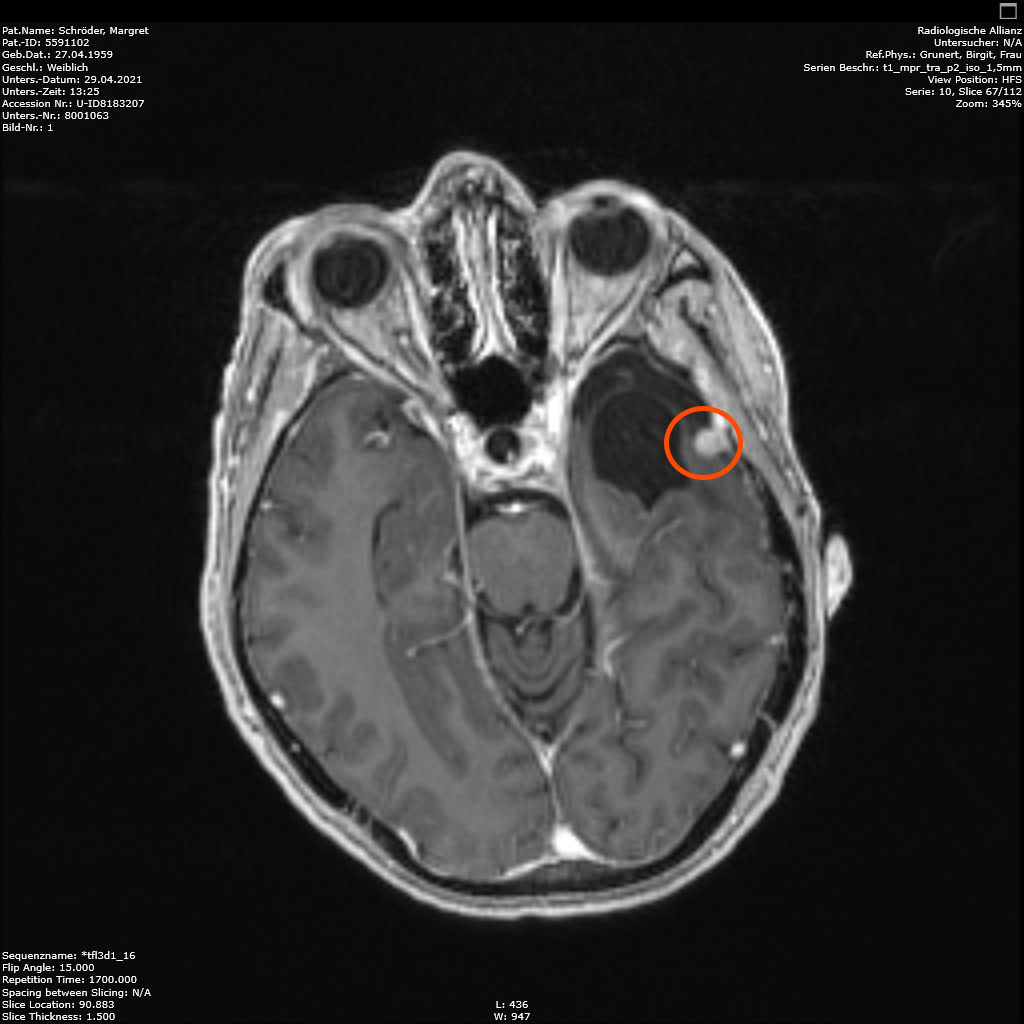

Am 03. November war mein Kontrollbesuch beim MRT. Leider ist ein kleiner Befund aufgetaucht. Schau das Video, dann kannst Du sehen.

Nun kann sich zeigen, ob die menschliche Medizin eine Lösung für mich hat. Möglichkeiten gibt es. Sogar mindestens eine, die der Neurochirurg als fein und elegant beschreibt. Gamma-Knife, eine Strahlentherapie. Klingt etwas nach Star Wars – man wird sehen, etwas abwarten ist auch drin.

Am 29.4.2021 war ich zum Kontroll-MRT drei Monate nach der hochmodernen Strahlentherapie, dem Gamma-Knife. Leider ist das Ergebnis: den Tumor hat diese Behandlung nicht beeindruckt, keine Änderungen zu erkennen. Der Arzt schlägt eine weitere Kontrolle in 6 Monaten vor. Ich finde es etwas schwer, dieses Ergebnis einzuordnen. Aber so ist es nunmal. Vielleicht ist es ja normal, und wird erst später gut (siehe Punkt 4).

Heute war ich im MRT im Bremen. Der Befund des auswertenden Arztes ist, dass er der Meinung ist, dass der Tumor etwas gewachsen ist. Ich habe mir die Bilder angesehen und versucht diese Aussage zu verstehen. Vermutlich ist sie richtig, aber das Wachstum ist nicht heftig nur vielleicht von 0,7 cm auf 0,8 cm. Aber Gamma-Knife hat es offensichtlich nicht entfernt.